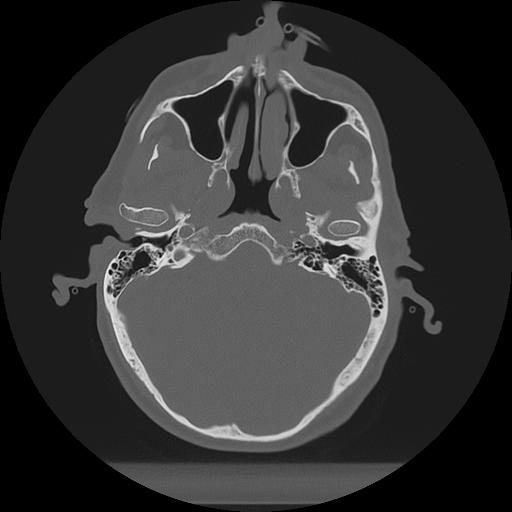

11 HUESO,,Axial,2.0,HUESO,,